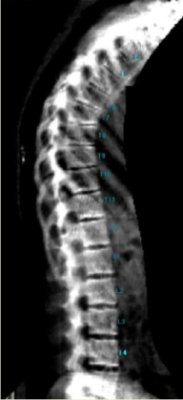

Podczas jednego badania przeprowadzony zostaje pomiar wysokości oraz ocena deformacji trzonów kręgowych w części piersiowej i lędźwiowej kręgosłupa (T4 – L4).

Aparat z wysoką precyzją analizuje, identyfikuje oraz klasyfikuje złamania trzonów kręgowych.

W badaniu morfometrycznym metodą DXA (VFA ang. Vertebral Fracture Assessment) w przeciwieństwie do tomografii komputerowej (KT) i rezonansu magnetycznego (MRI) standardowo dokonuje się obliczeń wysokości trzonów kręgowych (w cm) i porównuje się do normy właściwej dla płci, wieku i wzrostu.

Ramię densytometru przesuwa się nad ocenianym fragmentem kośćca. Na ekranie komputera pojawia się obraz kręgosłupa i dokonywany jest pomiar wysokości w cm oraz ocena deformacji trzonów kręgów części piersiowej i lędźwiowej kręgosłupa.